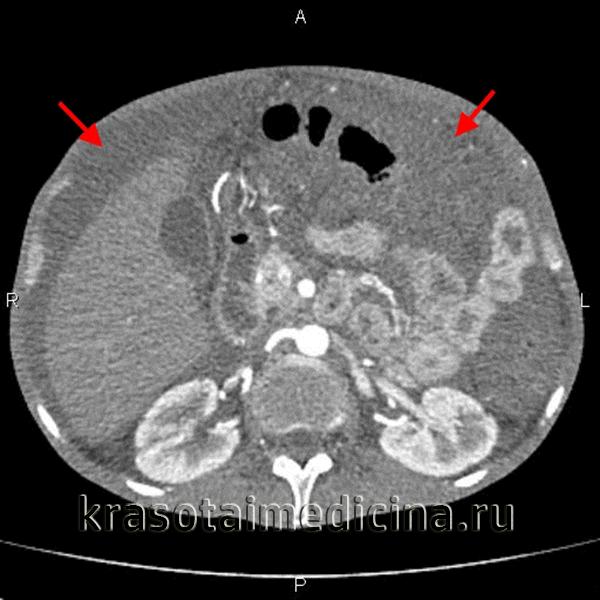

- обструктивная (подпеченочная) или механическая желтуха — причина желтого цвета кожи может заключаться в опухоли, кисте, увеличении лимфоузлов, образовании камней, скоплении паразитов, что приводит к сжатию или повреждению желчных протоков, и соответствующие компоненты желчи, включая билирубин, попадают в кровь.

Игорь, 48 лет: «У меня опухли ноги и появился большой живот, а также кожа стала желтоватой. Я не придавал этому значения несколько недель, но когда заметил, что желтизна нарастает, решил обратиться к специалисту. Врач заподозрил у меня проблемы с желчным пузырем. На контрастном обследовании оказалось, что есть блокировка. Теперь я на строгом режиме диеты и жду операции.»